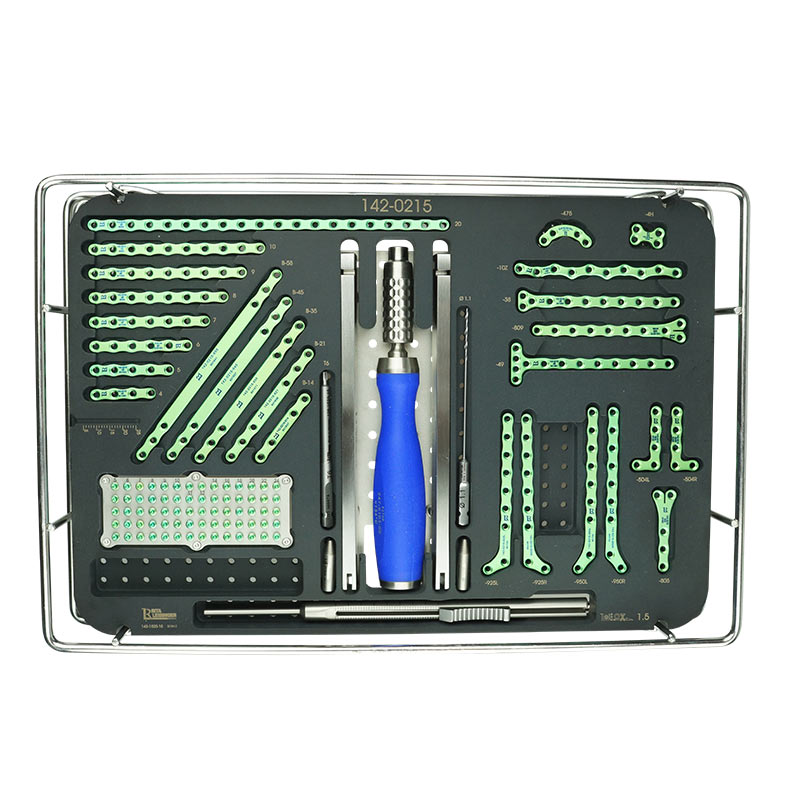

TTA RAPID®

Learn how to perform CCL Repair with TTA RAPID®

Dr. Yves Samoy shares with you his knowledge that he has gained since the beginning of TTA RAPID®. This online course is recorded with the same presentation materials used in the "live" wet-labs all around the globe. You may ask questions in the comments section of each chapter. Dr. Samoy will then receive an email with your question and follow-up with you that way.

This virtual course offers a long and detailed "real" surgery with live comments from Dr. Yves Samoy.

Tiny TTA RAPID®

Learn how to fix CCL Ruptures in Tiny Animals with the Tiny TTA RAPID® System

Dr. Hugo Schmökel shares with you all his knowledge about CCL Ruptures in Tiny Animals. It will be divided into a theoretical and a practical part. You may ask questions in the comments section of each chapter. Dr. Schmökel will then receive an email with your question.

The only difference between this online course and a wet-lab is the practical part. This course offers a long and detailed "real" surgery with the live comments from Dr. Hugo Schmökel. But you are required to practice on your own with cadavers.